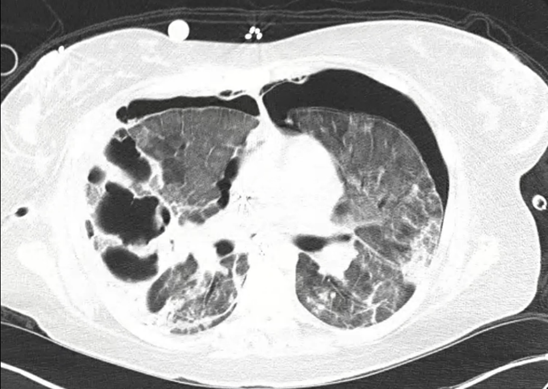

A 31-year-old woman G4P2204 was admitted with respiratory failure. Her laboratory work showed that her hemoglobin was 9.7 g/dl, D-dimer 1349 ng/mL fibrinogen equivalent units procalcitonin 0.44 ng/mL, C reactive Protein 91.4 mg/L, normal white count and her nasal reverse transcription-polymerase chain reaction was positive for SARS-CoV-2. Her Chest x-ray showed bilateral patchy airspace opacities. She underwent emergent cesarean section, was intubated and placed on mechanical ventilation. She was treated with Remdesivir, dexamethasone, vancomycin and piperacillin-tazobactam. On day 11 she developed bilateral pneumothorces which required placement of emergent chest tubes. There was a new elevation in white blood count (16,000/ul) and inflammatory markers. She reached threshold of mechanical ventilatory support so additional support with extracorporeal membrane oxygenation (ECMO) was initiated. On day 15 her Computed Tomography (CT) chest showed a large multiloculated cavity (Figure 1). She underwent Bronchoscopy with BAL and the cultures were noted to be positive for Mucorales (Lichtheimia species). A diagnosis of Pulmonary Mucormycosis was made. There was no evidence of invasive disease on CT abdomen-pelvis, CT head and nasal endoscopy. No tissue pathology was obtained. She was started on treatment with amphotericin B and posaconazole. On day 21 she underwent tracheostomy and successful ECMO weaning in addition to the removal of bilateral chest tubes. Amphotericin B was discontinued, and she was discharged on supplemental oxygen through nasal cannula and oral posaconazole. She continued to show clinical and radiological improvement on outpatient follow-up in clinic visits.

Figure 1: CT chest noted bilateral diffuse interstitial opacities with predominantly right sided large multiloculated cavitary lesion.